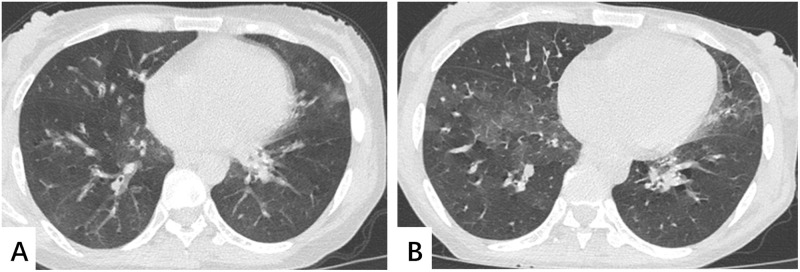

EGPA可影响多器官系统,通常以呼吸道症状为首发表现。缺乏特定的诊断性生物标志物使其容易误诊。本文描述了一位40岁的女性患者,她表现为哮喘样症状、神经感觉障碍、贫血、外周血嗜酸性粒细胞增多和肺部受累。诊断为EGPA合并AIHA。单纯糖皮质激素治疗无效后,加入免疫抑制剂环磷酰胺可缓解患者症状。总剂量达到7g后停用环磷酰胺,患者复发。患者的后续治疗包括糖皮质激素和MMF的联合治疗,没有复发的证据。本病例在临床上比较少见,所幸最终治疗效果令人满意。

EGPA can affect multiple organ systems, typically presenting with respiratory symptoms as the initial manifestation. The absence of specific diagnostic biomarkers makes it prone to misdiagnosis. This article describes a 40-year-old female patient who presented with asthma-like symptoms, neurosensory impairment, anemia, peripheral blood eosinophilia, and pulmonary involvement. The patient was diagnosed with EGPA combined with AIHA. After ineffective treatment with glucocorticoids alone, the patients' symptoms were relieved by the addition of the immunosuppressant cyclophosphamide. Cyclophosphamide was discontinued after the total dose reached 7g and the patient relapsed. Subsequent treatment for the patients involved a combination of glucocorticoids and MMF, with no evidence of recurrence. This case is relatively rare in clinical practice, and fortunately the final treatment effect is satisfactory.